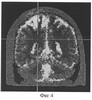

На фиг.3 изображен очаг нарушения перфузии головного мозга (ОНМК) по МРТ исследования.

После стабилизации общего состояние и выведения пациента из отделения интенсивной терапии пациенту было проведено обследования на магнитно-резонансном томографе для уточнения характера и интенсивности поражения головного мозга. Результаты обследования МРТ представлены на фиг.3: Зона усиленного Т2 – изображения МРТ в области отека коры, развившегося при ОНМК в послеоперационном периоде после выполнения трех сосудистого аортокоронарного шунтирования, без одновременной коррекции стеноза ВСА справа. Именно в данной зоне, на пике гипоксической пробы была выявлен очаг нарушения перфузии по данным электроимпедансной томографии.